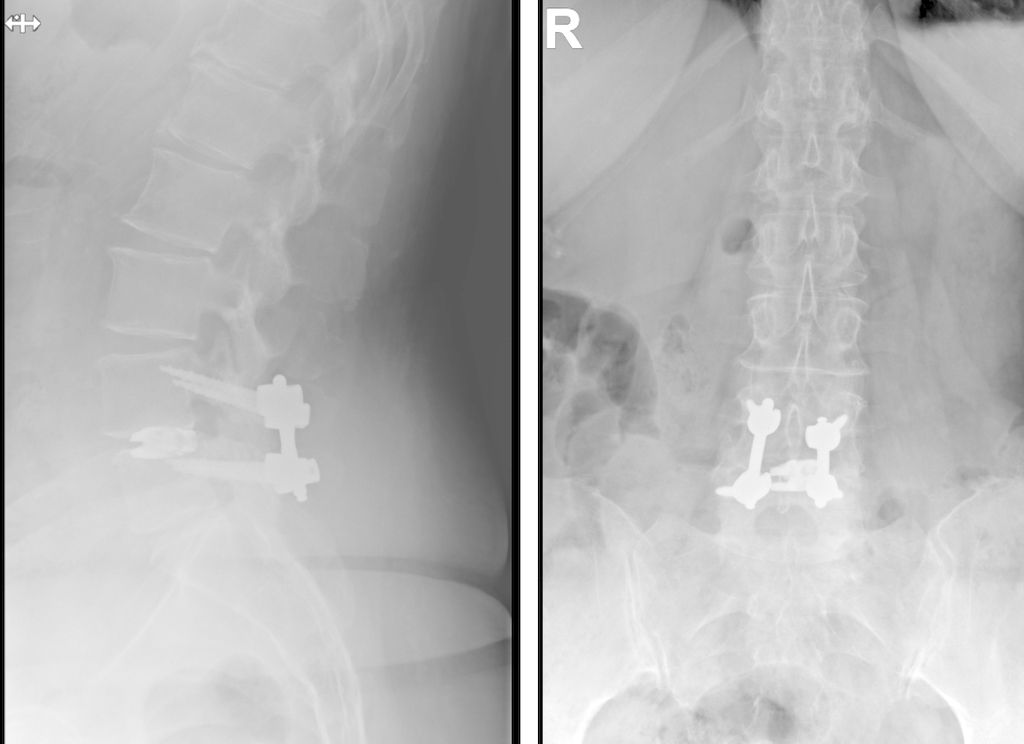

Beispiel für die Implantation zervikaler Pedikelschrauben. In diesem Fall kam es bei einem 61-jährigen Patienten 10 Jahre nach anteriorer zervikaler Diskektomie und Fusion (ACDF) C4/5 und ventraler Verplattung C4–6 zu einer Ankylosierung auch von C6/7. Nach Sturz kam es zu einer Fraktur bei C6/7 mit begleitender Bogenfraktur und auch Beteiligung der dorsalen Ligamenta (Abb. 1 und 2). Klinisch bestanden ausgeprägte Nackenschmerzen und kein neurologisches Defizit. Es wurde die Indikation der dorsalen Verschraubung von C4 auf Th1 gestellt. Intraoperativ wurde routinemäßig zusätzlich eine kleine Referenzschraube in einer Lamina – entfernt von der Dornfortsatz-Referenzklemme für die Navigation – gesetzt. Mit dieser konnte intraoperativ die Genauigkeit der Navigation exakt überprüft werden (Abb. 4 und 5). Mittels navigierter High-Speed-Fräse wurden die Schraubenkanäle vorgebohrt (Abb. 6), im Anschluss wurde der Bohrkanal ausgetastet und die Schrauben wurden implantiert. Abbildung 7 zeigt eine Röntgenkontrolle 3 Monate postoperativ.

TLIF über Mittellinienzugang mit Schrauben in „cortical bone trajectory“. Bei der 63-jährigen Patientin bestand eine degenerative Spondylolisthese Meyerding Grad I mit Facettengelenkszysten und Wirbelkanalstenose (Abb. 8). Klinisch bestanden Lumboischialgien mit Ausstrahlung dem Dermatom L5 bds. entsprechend. Es wurde ein Mittellinienzugang durchgeführt und zuerst wurden navigierte Schrauben in „cortical bone trajectory“ platziert (Abb. 9). Anschließend erfolgten eine Facettektomie L4/5 links und eine Dekompression des Wirbelkanals. Abbildung 10 zeigt, dass der Hautschnitt aufgrund der mittelliniennahen Schraubenköpfe klein gehalten werden kann. Klinisch wurden die lumbalen Schmerzen wie ausstrahlende Beschwerden 1 Jahr postoperativ annähernd vollständig behoben, die korrespondierende Röntgenkontrolle ist in Abbildung 11 dargestellt.